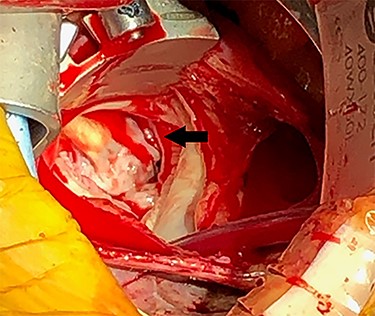

Eight months after MitraClip implantation, the patient underwent MV replacement via a minimally invasive right thoracotomy. The patient underwent cardiopulmonary bypass via the femoral vessels. Through a right thoracotomy, a left atriotomy was made. The previously placed mitral clips were associated with fibrotic changes and damage to the leaflets (Figs 2 and 3). The left ventricle was noted to be severely dilated. The MV was replaced with a 25-mm bovine pericardial bioprosthesis. Cardiopulmonary bypass was terminated at the conclusion of the operation with moderate inotropic support and satisfactory hemodynamic parameters. The intraoperative transesophageal echocardiogram showed mild improvement of LVEF from 20 to 30%. The bioprosthetic mitral valve was functioning appropriately without para-valvular leak and a transvalvular gradient of <2 mmHg. Postoperative transthoracic echocardiogram revealed an LVEF 30–35% and a normally functioning bioprosthetic MV with a mean transmitral gradient of 5 mmHg. The patient was extubated, weaned off inotropic support, and transferred out of the intensive care unit on post-operative days two, four and seven, respectively. She was ultimately discharged to home with home services. Her echocardiogram remained stable at time of discharge and 1 month follow-up. At 6 months postoperatively, the patient continued to progress with one brief hospital admission for non–cardiac-related concern.